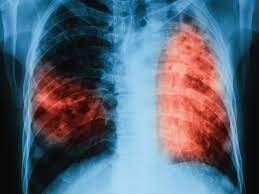

Aumentan los casos de tuberculosis en Córdoba

Las autoridades sanitarias de Córdoba reportaron un incremento preocupante en los casos de tuberculosis, con un total de 140 casos en lo que va de 2024

Según la Dirección de Epidemiología de la Municipalidad de Córdoba, 54 de estos pacientes están actualmente bajo tratamiento en el Programa Municipal de Tuberculosis, que funciona en colaboración con los programas provinciales y nacionales. Las autoridades han enfatizado la necesidad de reforzar las medidas de prevención y detección temprana de la enfermedad para controlar su propagación.

A pesar de la percepción común de que la tuberculosis es una enfermedad del pasado, las autoridades subrayan que sigue siendo un problema de salud pública a nivel local, nacional e internacional. La enfermedad, se transmite a través del aire cuando una persona infectada tose, estornuda, habla o canta, poniendo en riesgo a quienes conviven en espacios cerrados.

La detección temprana es clave para el tratamiento y la cura de la tuberculosis. Los especialistas advierten que muchos de los casos detectados en Córdoba corresponden a personas jóvenes en edad productiva, quienes a menudo ingresan al sistema de salud en un estado avanzado de la enfermedad. Esto subraya la importancia de los controles periódicos, especialmente en contextos de desigualdad y hacinamiento, donde la enfermedad tiende a proliferar.

Entre los síntomas más comunes de la tuberculosis se encuentran la tos persistente con flema por más de 15 días, dolor en el pecho, debilidad corporal, pérdida de peso y sudoración nocturna. Ante la presencia de estos síntomas, es fundamental realizarse pruebas diagnósticas para iniciar el tratamiento a tiempo.

En Argentina, la vacuna BCG es obligatoria y se administra de manera gratuita a todos los recién nacidos, ya que es efectiva en la prevención de las formas graves de tuberculosis. Las autoridades recomiendan mantener las medidas de prevención y estar atentos a los síntomas para evitar la propagación de esta enfermedad.